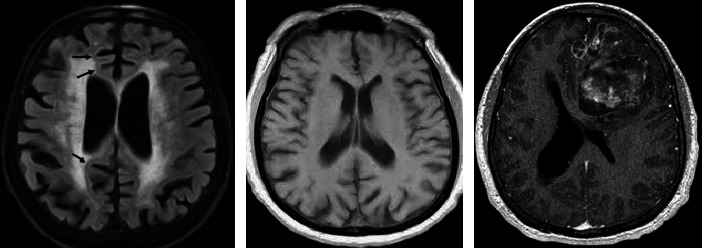

Abstract Image